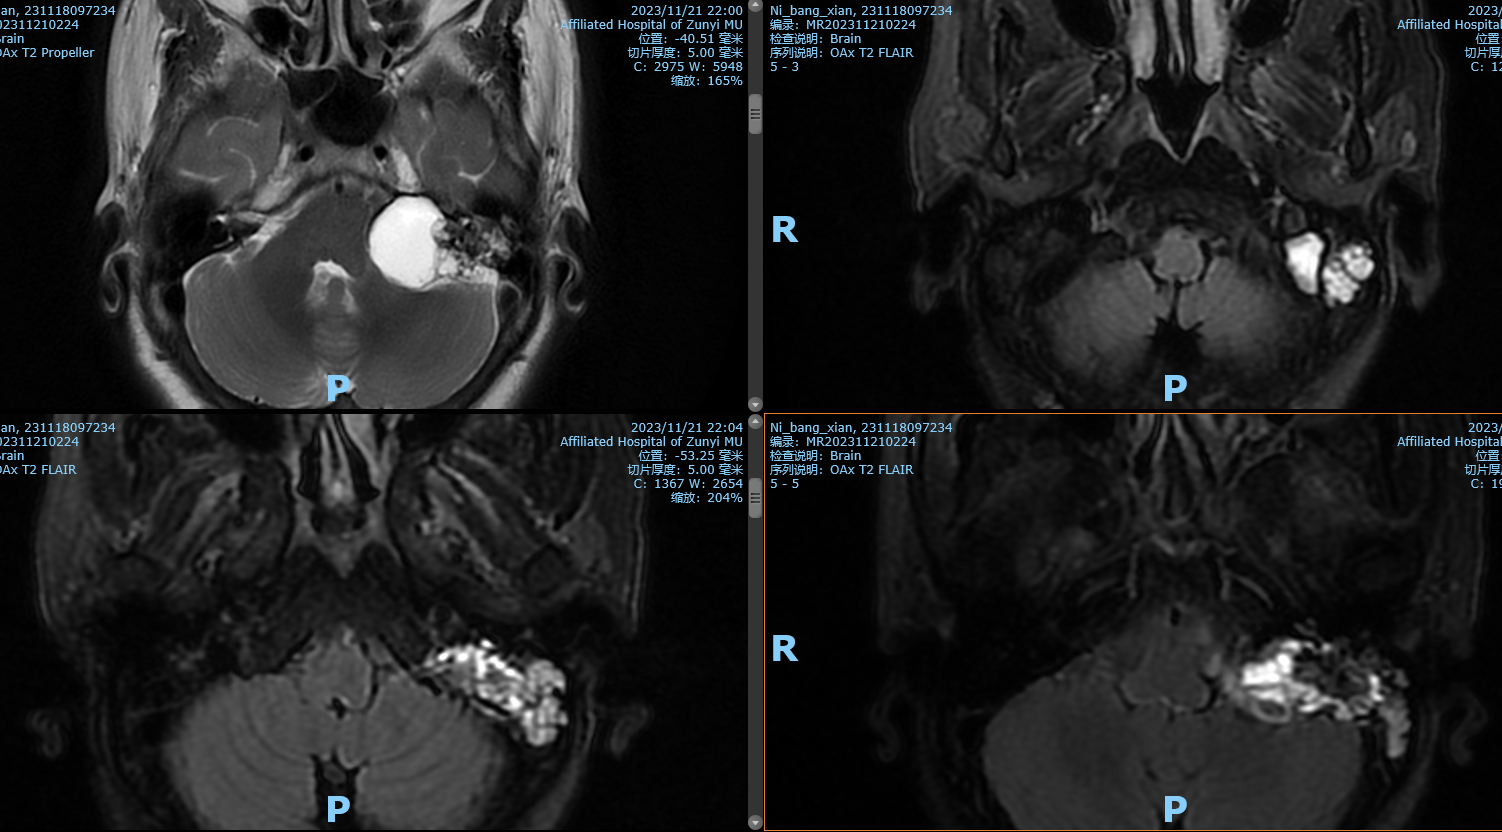

56岁女患,因“口角右歪伴左眼闭合不全18个月”入院。查体:生命体征平稳,双侧瞳孔正常,光反射灵敏,左眼闭合不全,左侧额纹、鼻唇沟消失,口角右侧歪斜。House-Brackmann(H-B)分级 :IV级四肢肌力5级,肌张力无异常,生理反射存在,病理反射未引出。颅脑MRl:1左侧桥小脑角区占位,考虑听神经鞘瘤伴囊祥变。

阅片后考虑为左侧内淋巴囊肿瘤,侵犯岩骨,破坏面听神经,手术方案选择:左侧乙状窦前入路,窦前入路切除CPA区肿瘤,同时做岩骨次全切,术中发现面神经破坏,截取左侧耳大神经作为桥接神经,行左面-舌下神经端侧吻合,关颅后发现左侧外耳道与颅内相通,脑脊液缓慢流出,又在神经内镜下行外耳道缝扎术,术后2周出院,无脑脊液耳漏、鼻漏。术后病理后免疫组化证实为内淋巴囊肿瘤,ki-67达20%。

影像学检查:ELST起源于内淋巴囊或内淋巴管,因此早期以岩锥后缘后半规管后方内淋巴囊部位为中心生长,逐渐侵蚀颞骨其他部位。